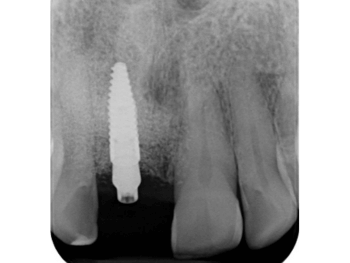

In diesem Fall hätte eine Brückenversorgung in regio 11 viel gesunde Zahnhartsubstanz gekostet. Daher fiel die Entscheidung der Patientin auf eine Implantatkrone. Neben des wiederholten Bruchs der Interimsprothese aufgrund des Tiefbisses stellte die provisorische Versorgung aufgrund der Lage im Frontzahnbereich hohe Anforderungen. Die Patientin verfügt überdies über eine hohe Lachlinie, bei der die Gingiva komplett sichtbar ist. Um den ästhetischen Ansprüchen gerecht zu werden, war eine gründliche Planung und längerer Vorlauf erforderlich. Das Ziel war nicht nur, ein ästhetisch befriedigendes Ergebnis zu liefern, sondern dieses auch langfristig zu erhalten. Deswegen dauerte die Vorbehandlung mit Socket Preservation, PA-Behandlung, Augmentation, Implantation und Gingivaformung durch die provisorische Krone insgesamt neun Monate.